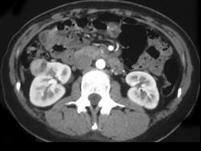

问题 男,58岁,无痛性肉眼血尿1个月余,请结合CT图像作出诊断 ( )

选项 A、右肾血管平滑肌脂肪瘤 B、右肾黄色肉芽肿性肾盂肾炎 C、右侧囊性肾癌 D、右肾结核性肉芽肿 E、右侧肾癌

答案 E